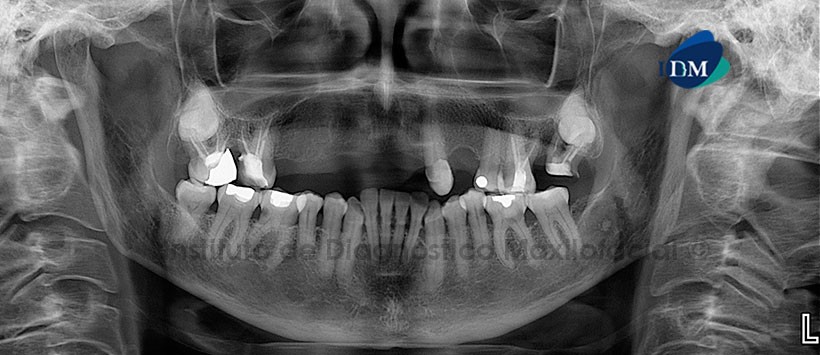

Paciente de 68 años de edad acude al Instituto de Diagnostico Maxilofacial para evaluación de general.

A la evaluación de la radiografía panorámica, se aprecia la ausencia de piezas dentarias (15, 14, 13, 12, 11, 21, 22, 24 y 38) Así mismo se aprecia reabsorción ósea moderada del proceso dentoalveolar bimaxilar, lesión cariosa en piezas 36, 35 y 46, material de obturación en piezas 16, 17, 26 y 27. Siendo lo más resaltante las piezas 18 y 28 las cuales están impactadas proyectadas sobre los segmentos radiculares de las piezas 17 y 27 respectivamente.

Con la tomografía volumétrica de haz cónico, se obtuvo una reformación panorámica en MIP (Proyección de Máxima Intensidad) donde evidenciamos lo anteriormente descrito. En los cortes axiales se evidencia que el segmento coronario se localiza entre las raíces de las piezas 17 y 27. Así mismo en los cortes transaxiales y tangenciales podemos notar que la orientación de ambas piezas es hacia la zona lingual, también observamos que ambas piezas están en contacto con la raíz de las piezas 17 y 27 respectivamente sin ocasionar ningún tipo de alteración aparente a las estructuras óseas ni dentales adyacentes.

En las reconstrucciones tridimensionales vemos de manera ilustrativa la correcta posición de las piezas previamente mencionadas, así como la repercusión de estas sobre las estructuras óseas y dentales adyacentes.

Conclusión: Terceras molares impactadas en maxilar superior.